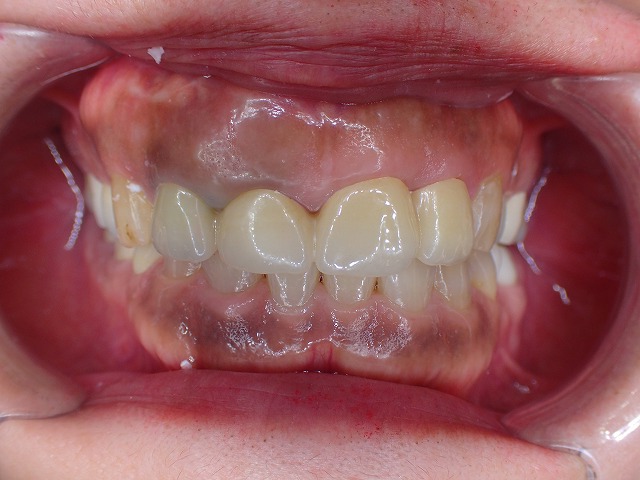

来院時の状態

問題の歯は、過去に根尖切除が行われており、被せ物がしばしば外れていました。

さらに、歯ぎしりの影響も強く、被せ物自体に大きな負担がかかっていました。

詳しく確認すると、根の先に近い部分は非常に厳しい状態で、

歯の保存が簡単ではないことが分かりました。

根尖切除の履歴のある歯が脱離して来院

歯ぎしりもひどく何度も脱離しています。

歯ぎしりでメタルボンドクラウンに

穴が空いています。